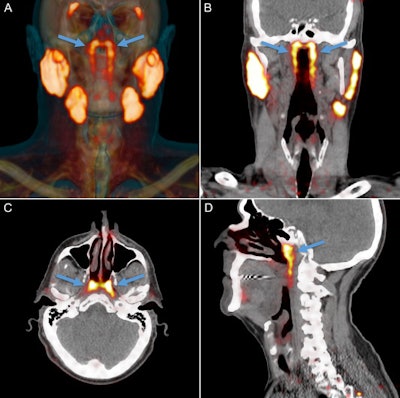

PSMA-PET/CT can visualize salivary glands with high sensitivity and specificity, Valstar and colleagues wrote. This allowed the researchers to observe an unknown bilateral structure posterior in the nasopharynx, with radiopharmaceutical uptake much like that of the known major parotid, submandibular, and sublingual salivary glands.

All 100 patients with prostate or urethral gland cancer demonstrated a divided bilateral PSMA-positive area with an average length of 4 cm. Examining the glands and 3D reconstruction confirmed the presence of PSMA-expressing, predominantly mucous glands with multiple draining ducts. They were found predominantly near the torus tubarius, according to the authors.